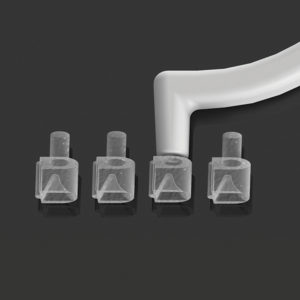

ALASTIC MEDIO PERLADO X 1.5MTS- MORELLI

La cadena de elastómeros ortodónticos, son empleados como promotores de fijación de arcos ortodónticos a las ranuras de los brackets, promoviendo el trazado de los elementos dentales y transferencia de las fuerzas aplicadas por los arcos para corrección de las maloclusiones.